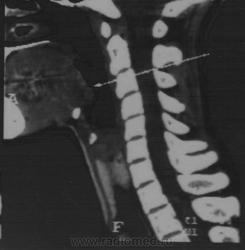

Пациентка 33 года,обратилась с жалобами на чувство инородного тела в гортани,наличие  "кома в горле"в течение 2 х лет.Причину не указывает.Ранее не лесилась.Беременность 5-6 нед. Обследована:эндоскопия ЖКТ без потологии,Лор патологии не выявлено,ФОГ в норме,УЗИ щитовидной железы без патологии. КТ для обсуждения.

2 года "ком в горле", а КТ во время беременности. Даже не забавно... Стрелками указано накопление контраста в язычной миндалине. Скорее гипертрофия+обострение воспаления.

Как гипертрофию язычной миндалины ).Причем ЛОР не видит этой патологии.(В заключении норма).Дама ,к сожалению,согласие не подписывала,и беременность сохранять не будет.Диагноз не установлен.